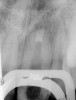

Clinical procedure: If apical bone loss is present (Figure 1) a collagen/gelatin sponge (eg, Gelfoam®, Pfizer Inc., www.pfizer.com) can be placed apically so that the MTA can be delivered to the desired working length. (Any other surgical resorbable sponge would also work, such as OraPlug® [Salvin Dental Specialties, www.salvin.com], Surgifoam® [Midwest Dental, www.mwdental.com], or Surgispon® [Aegis Lifesciences, www.surgispon.com]). This is done by taking a small piece (2 mm x 2 mm) of the resorbable sponge and pushing it down to and through the root apex with an endodontic file. Once this is done, MTA is packed down the canal with a custom-fitted cone. The clinician can use a rubber stopper on the gutta-percha cone to know the exact length of MTA placed in the apical third (Figure 2). Once the apical third is sealed with 3 mm to 5 mm of MTA, the remaining coronal canal space can be back-filled using a warm gutta-percha technique (Figure 3).

Fig 2. MTA placed in the apical third.

Figure 2

Fig 3. Postoperative radiograph.

Figure 3